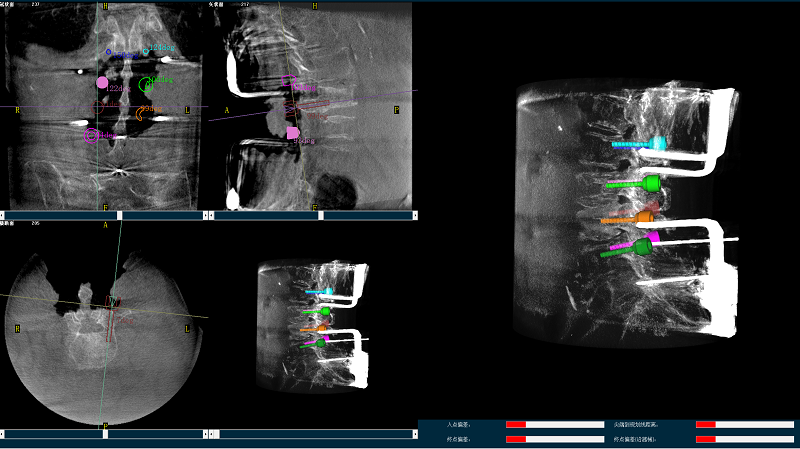

三維圖像

(2)使用普愛醫療平板三維C形臂掃描患者,得到術中三維圖像并傳送至骨科機器人導航系統。骨科機器人導航系統基于高清術中三維圖像進行手術規劃。

手術規劃圖像